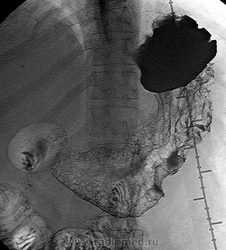

06.06.2011 Рентгеноскопия желудка и КТ-органов брюшной полости.

Пациент 52 года, жалобы на боли в эпигастрии.

Рак большой кривизны с мтс печени?

Представленный случай конечно уже запущенный, аденокарцинома по большой кривизне желудка с множественным метастазирвоанием паренхимы печени, кстати на КТ четко видно утолщенную инфильтрированную стенку желудка.